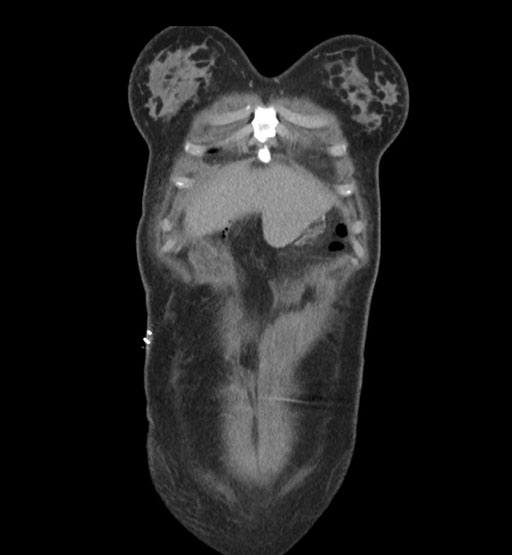

Coronal Arterial

Coronal Venous

Imaging analysis

Based on initial findings, which issue(s) would you be most concerned about?